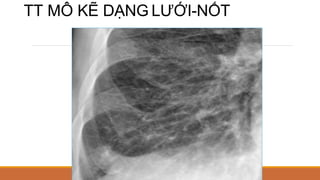

TỔN THƯƠNG MÔ KẼ

ĐN: có dịch, tế bào bất thường trong khoảng kẽ

NGUYÊN NHÂN:

◦ TỔN THƯƠNG MÔ KẼ DẠNG ĐƯỜNG: suy tim (T)

◦ DẠNG NỐT: lao, di căn

◦ DẠNG TỔ ONG: xơ phổi, bụi phổi…

BIỂU HIỆN TT MÔ KẼ

DẠNG ĐƯỜNG:

◦ KERLEY A: đỉnh, trung tâm, hình cung, dài #3-5cm, dày #3-4mm, bản chất là dày

mô kẽ trục PQ-MM

◦ KERLEY B: đáy, ngoại biên, vuông góc màng phổi, dài #2cm, dày <2mm, bản

chất là mô kẽ ngoại biên (vách liên tiểu thùy)

◦ KERLEY C: chồng nhau của Kerley A vàB

DẠNG BÓNG MỜ:

◦ Nốt: nhỏ, lớn

◦ Lưới, lưới-nốt, tổ ong

TT MÔ KẼ DẠNG LƯỚI-NỐT